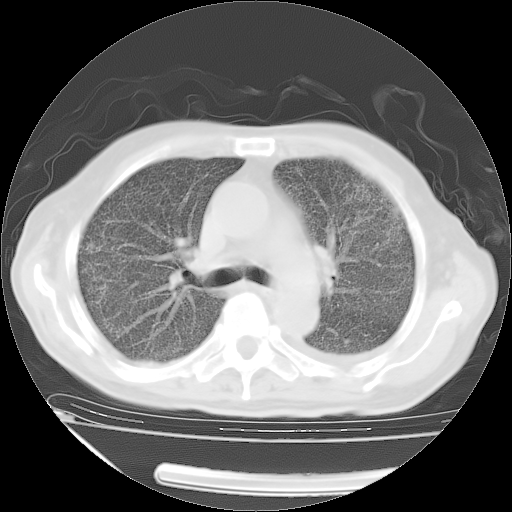

经过24天治疗,岳父的病情基本稳定。生活基本可以自理,可以下床活动。呼吸困难早已消失。体温基本正常。

只是甲强龙用80mg时血小板升到正常,改为60mg后又降到63×10*9/L。

主要治疗甲强龙80mg×14天,60mg×10天;同时抗结核(异烟肼+利福平+乙胺丁醇)。环磷酰胺0.1 tid 10天。

特别感谢胡教授、高管、桃子版主给出关键的治疗建议。桃版把所有肺部影像和全部临床资料请所在医院呼吸科、感染病科、结核科、临床免疫科专家会诊。临床免疫科专家制定了完整的治疗方案。